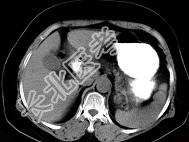

- 单项选择题女43岁上腹不适多年,体检行CT扫描如图, 最可能的诊断为 ( )

A、胃癌

B、胃平滑肌瘤

C、胃平滑肌肉瘤

D、胃淋巴瘤

E、胃蛔虫团块

- 女43岁上腹不适多年,体检行CT扫描如图